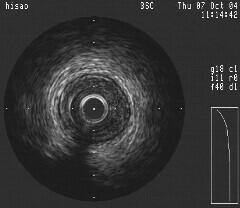

>○○先生; ところで、このIVUSのLowの物って動いていましたか?時期的には

Black holeよりはやはり血栓が考えやすいと思うのですが、血栓にしては形態がどうか

なっと悩んでしまいますステント内血栓ってもう少しもやもやしてるよな印象があるの

ですけど・・・ちなみにこの病変に対しては何か治療されましたでしょうか?

IVUSの静止画だけではわからないのですが、めちゃめちゃ固定されておりました。5つ

のコブがCypherの内側に向かって突出しているようなかんじです。私が考えるにこのま

ま放っておけばこぶがどんどん突出して閉塞しまうのではないかと勝手に解釈してま

す。(だからSATなのではないでしょうか?)しかし想像の域をこえません。(Case

”なまこ”も”Black Hole"も慢性期にできるものと個人的にはり理解してます。特に

○○先生のIVUSの本のP68にのっているBlack Holeの写真にそっくりですし、、、。し

かし3日で完成してますし、ステント留置で完全になくなってます。またよく見ると5つ

のコブはステントストラットの上にきれいに乗っているような気がしてなりません。個

人的には血栓と考えたいところです。みなさんはどおお考えでしょうか?IVUS上の所見

はecho lucentで似てますのでもしかしたら、構成成分で類似したのもあったのかもし

れません。ステントで末梢に流れてしまったとおもわれますが、病理がないので非常に

残念です。

実際はCypher3.5/8mm/20atmをいれても全然フローは保たれてましたし、小さな枝の抹

消塞栓もみられませんでした。最初のIVUSイメージで11時にあるコブがIVUSのプローブ

がはいったためか上半分がかけているように見えます。NIHではこんなことはおこらな

いでしょうから、おそらく非常にやわらかいけど可動性がないレベルの硬さではないか